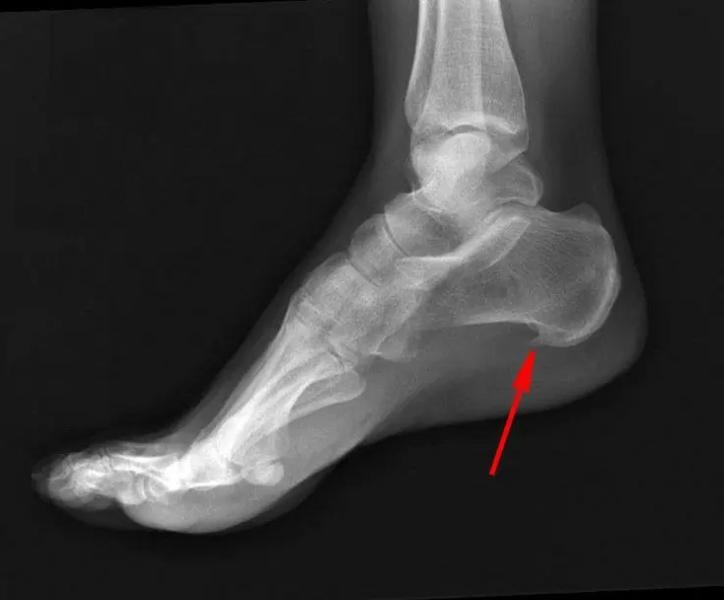

У кого было «пяточная шпора»?

К кому нужно обратить?

К Ортопеду?